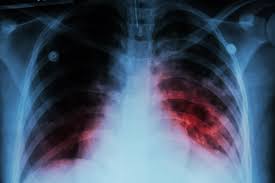

The training was organized in partnership with the Anambra State Ministry of Health and received support from the Global Fund. Medical experts at the event explained that TB is an airborne disease caused by the bacterium Mycobacterium tuberculosis. It primarily affects the lungs but can also harm other parts of the body. The disease spreads when an infected person coughs, sneezes, or talks, releasing bacteria into the air.